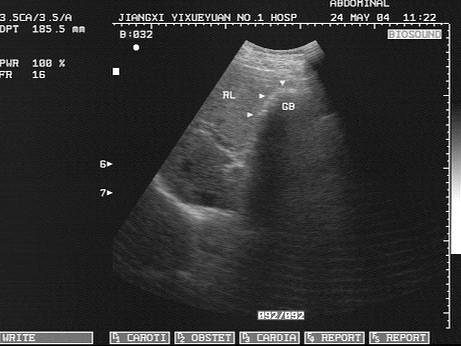

问题 男,60岁,上腹疼痛不适数10年。结合超声声像图,诊断为?(?)

选项 A.胆囊多发性结石 B.胆囊多发性息肉 C.胆囊泥沙样结石 D.胆囊充满性结石并萎缩性胆囊炎 E.胆囊胆固醇结晶

答案 D